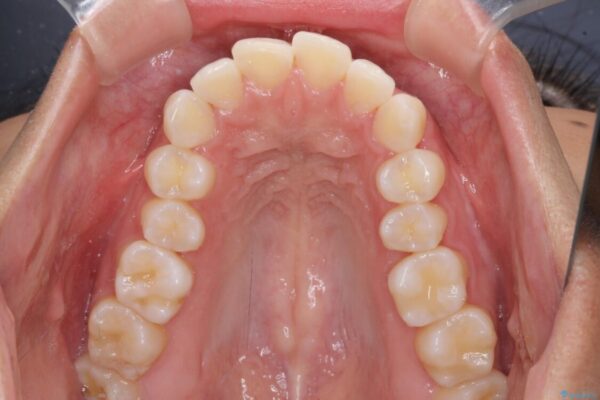

治療後

抜歯スペースに前歯を移動させることで歯の突出感が改善され、非常に唇が閉じやすい仕上がりとなりました。